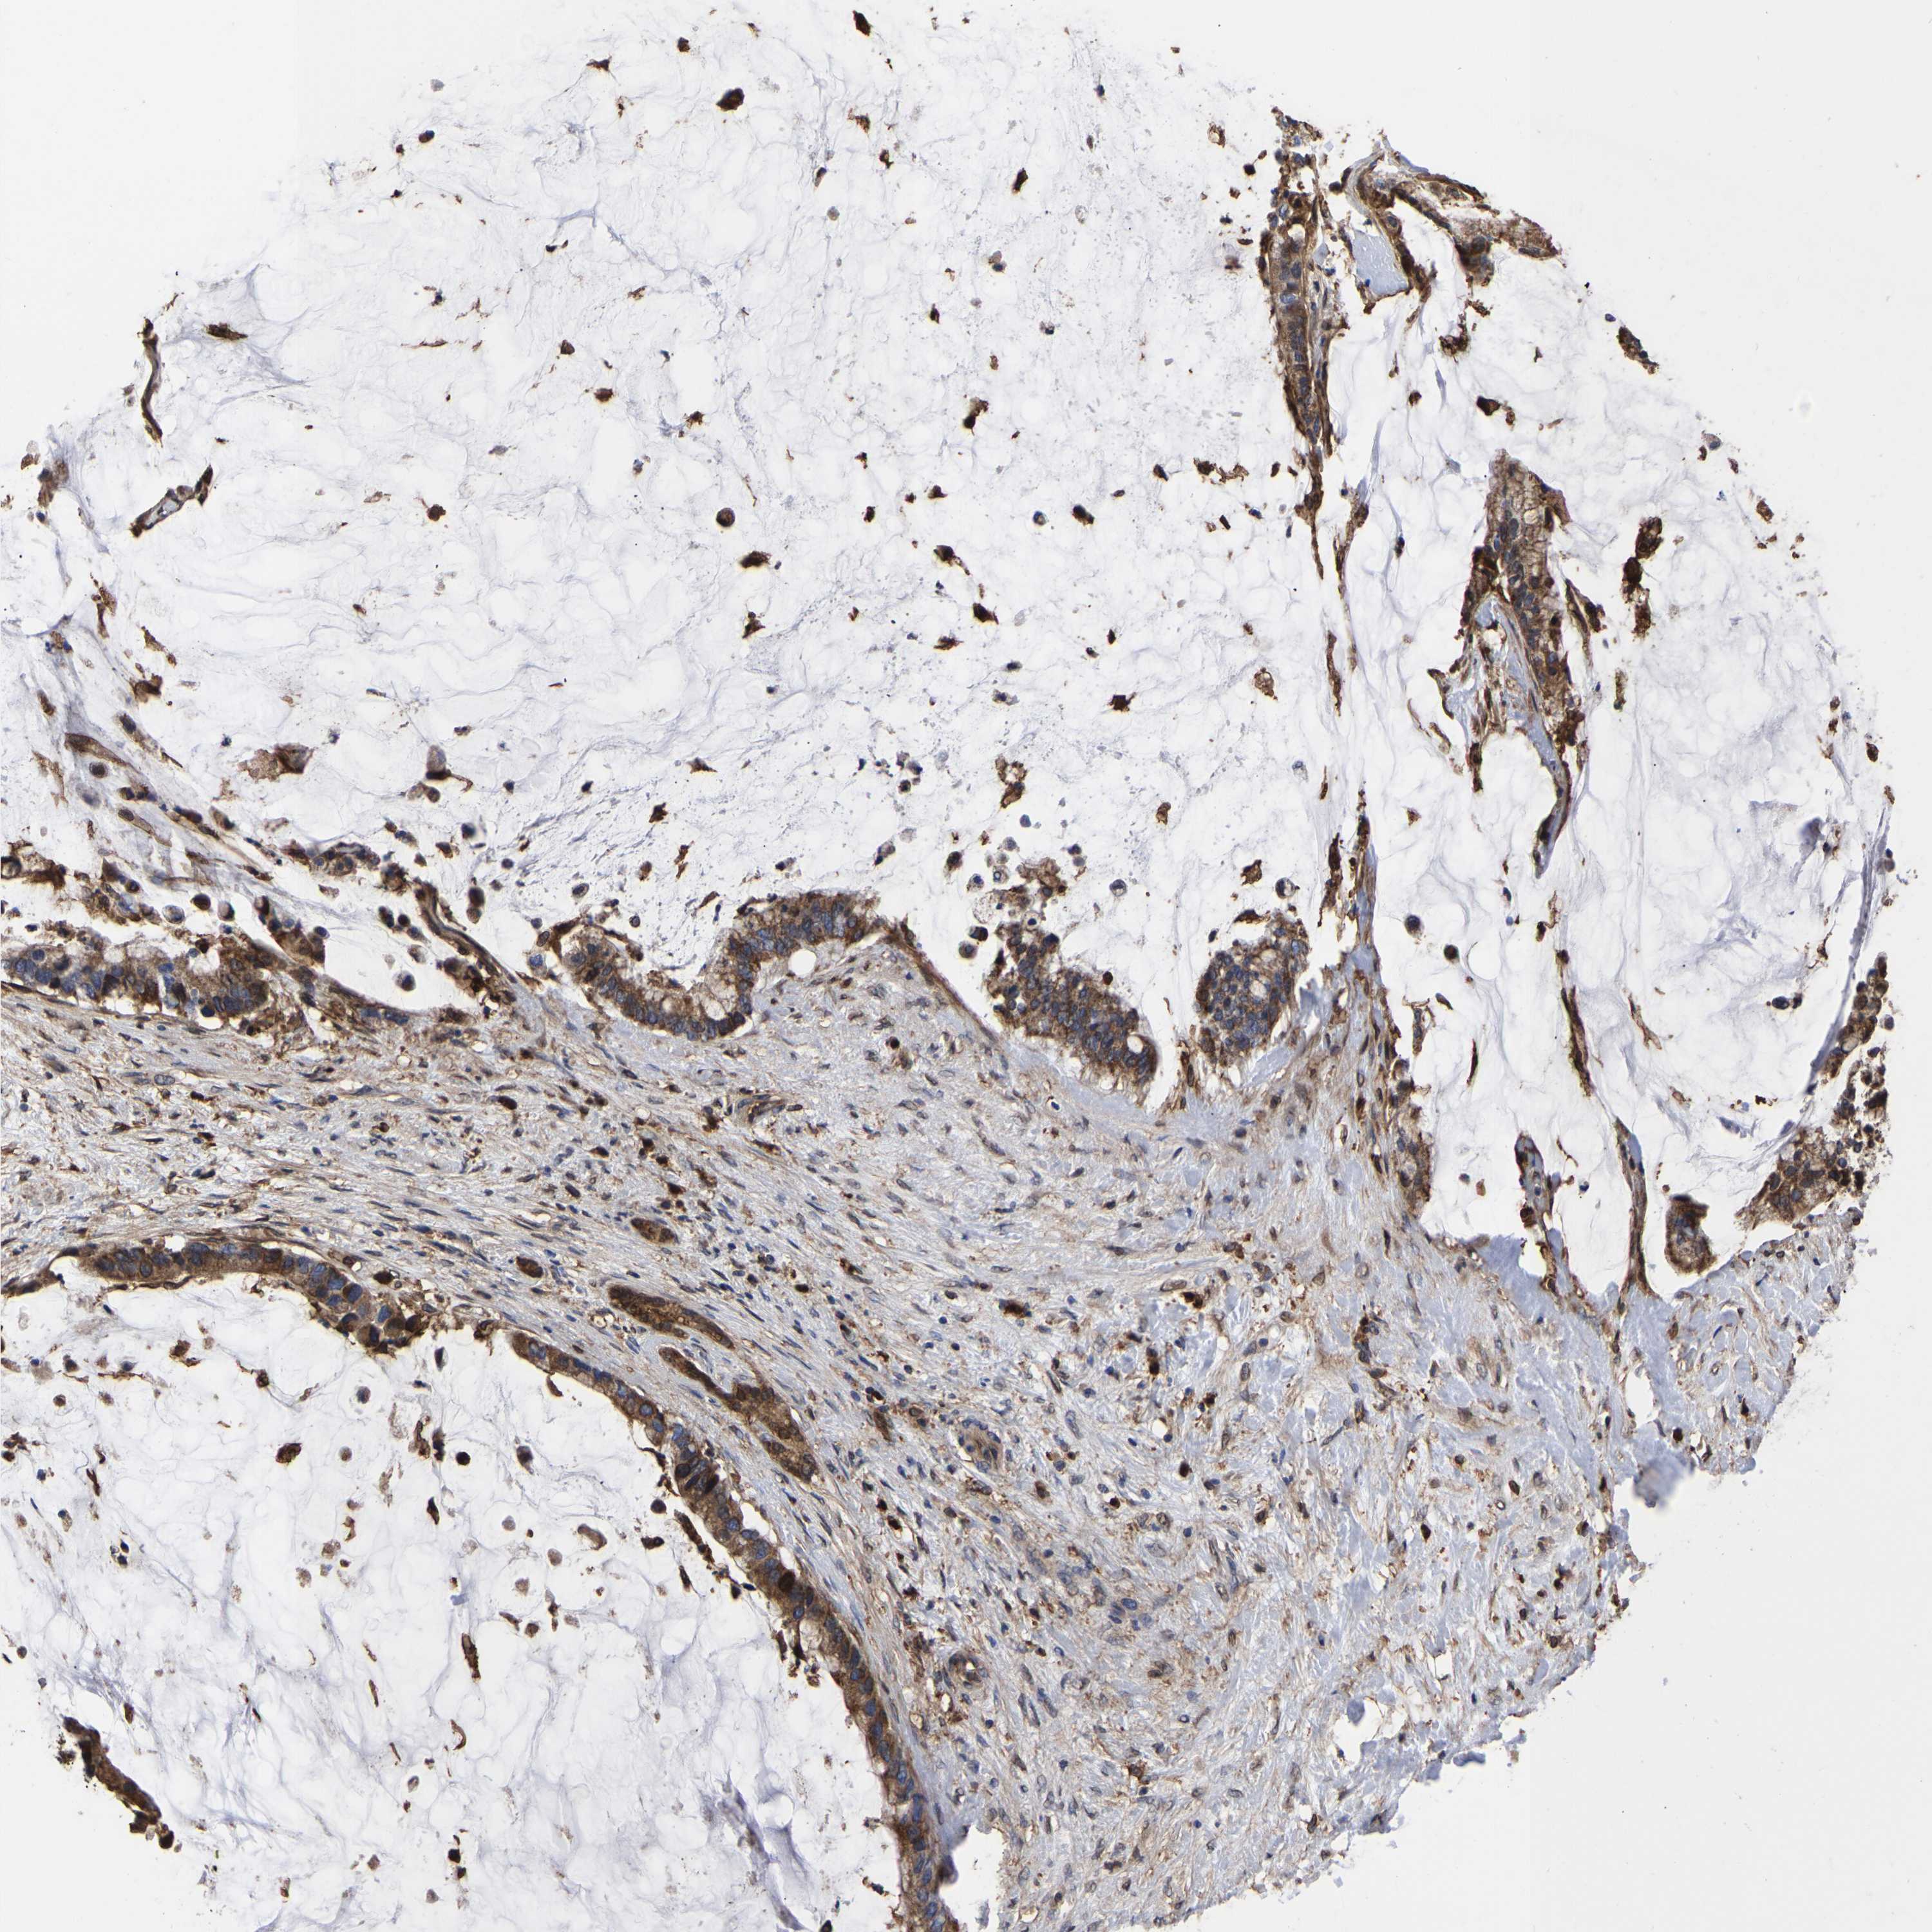

PANCREATIC CANCER - Protein expressioni

A mouse-over function shows sample information and annotation data. Click on an image to view it in a full screen mode. Samples can be filtered based on level of antibody staining by selecting one or several of the following categories: high, medium, low and not detected. The assay and annotation is described here.

Note that samples used for immunohistochemistry by the Human Protein Atlas do not correspond to samples in the TCGA dataset.

Antibody stainingi

Antibody staining in the annotated cell types in the current human tissue is reported as not detected, low, medium, or high, based on conventional immunohistochemistry profiling in selected tissues. This score is based on the combination of the staining intensity and fraction of stained cells.

Each image is clickable and will lead to virtual microscopy that enables deeper exploration of all samples and also displays staining intensity scores, fraction scores and subcellular localization as well as patient and tissue information for each sample.

Antibody HPA018844

Staining

High

Medium

Low

Not detected

Intensity

Strong

Moderate

Weak

Negative

Quantity

>75%

75%-25%

<25%

None

Location

Nuclear

Cytoplasmic/membranous

Cytoplasmic/membranous,nuclear

Adenocarcinoma, NOS